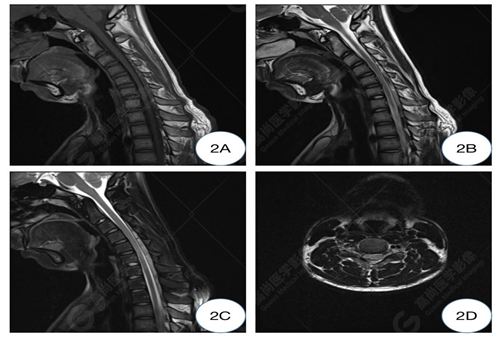

2A-2C圖、曲頸位T1WI及T2WI矢狀位圖示C5-6水平頸髓變細明顯,后方硬脊膜向前移位,并壓迫頸髓,硬膜外間隙增寬并其內(nèi)見條索狀低信號影;2D圖、曲頸位T2WI橫軸位圖示C5-6水平椎管變窄,相應(yīng)水平頸髓形態(tài)變扁平,呈受壓改變。

C5-6椎體水平頸髓及曲頸位頸椎異常改變,可符合平山病表現(xiàn)。

影像學(xué)常規(guī)中立位可表現(xiàn)為下頸椎和頸背交界處的脊髓萎縮變平,神經(jīng)膠質(zhì)增生區(qū)域在T2WI序列顯示為高信號,有時僅表現(xiàn)出可疑征象,需補充屈曲位掃描。HD 在屈曲 MRI 上具有特征性的成像特征。屈曲位MRI顯示,低位的頸髓向前移位,受壓變扁平,可合并萎縮,后部的硬腦膜向前移位,后硬膜外間隙增寬,形成新月形區(qū)域,并有異常信號改變及流空血管影,增強掃描硬膜外異常信號常呈明顯強化,提示其為充血的后靜脈叢可能,因為其在中立位掃描時完全消失。